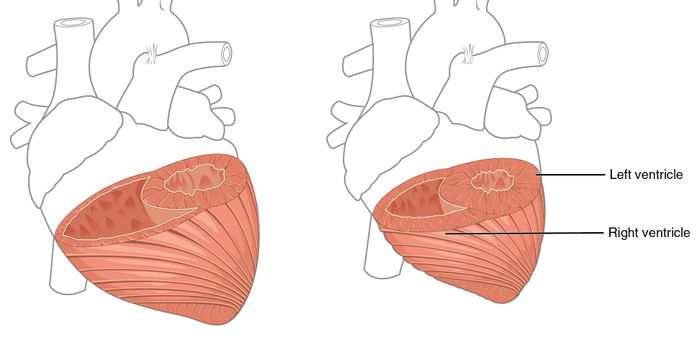

FEB 15, 2017CardiologyThe heart’s four chambers, made up of left and right atria and ventricles, work together in an amazingly intricate ...